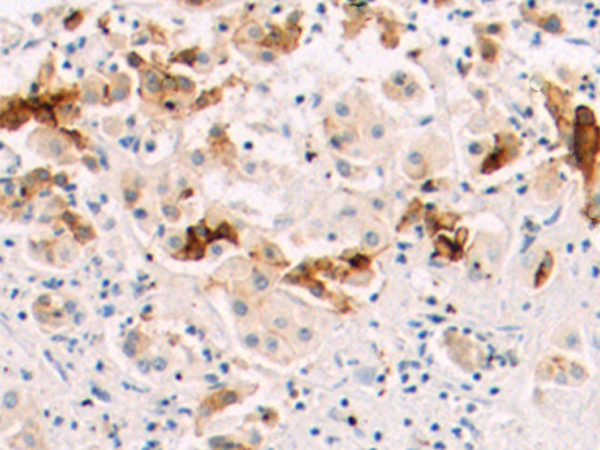

分类: 科研抗体货号: P00225别名: CMH7; RCM1; cTnI; CMD2A; TNNC1; CMD1FF应用: WB,IHC反应种属: Human, Mouse, Rat